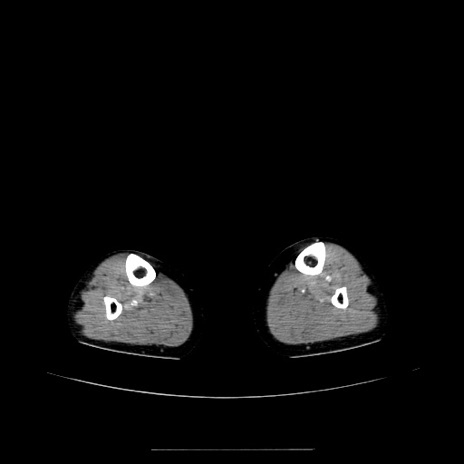

【症例】70歳代女性

【主訴】お腹が張る

【現病歴】1週間くらい前から腹部膨満の自覚あり。昨日夜から増悪したため、本日救急外来受診。

【身体所見】意識清明、BT 36.5℃、BP 165/106mmHg、HR 80bpm、SpO2 98%、腹部:膨満、軟、自発痛・圧痛なし、触診にて不快感あり、腸蠕動音:減弱

【データ】WBC 12600、CRP 1.04